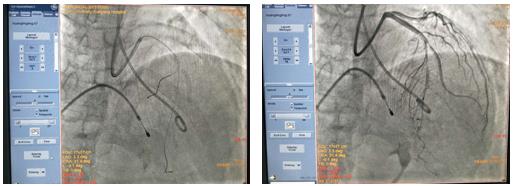

經過反復討論后,吳棟梁主任醫師作為手術指導者,在崔旭輝主任醫師團隊操作下,最終決定在臨時起搏器保護下行冠狀動脈造影術及心臟化學消融術。術中通過造影確認第二穿隔支未消融靶血管,測壓顯示左室壓222/13mmHg,主動脈壓136/88 mmHg,壓力階差86mmHg。經SPRINTER OTW球囊緩慢注入無水酒精0.8ml,10分鐘后復測左心室及主動脈壓分別為162/12 mmHg、123/82 mmHg,術后第5天,患者未訴胸悶、氣短、心悸等不適,復查心臟彩超示:EF:63%,FS:34%,收縮期左室流出道血流速度增快,Vmax:436cm/s,PG:76mmHg,二尖瓣反流長度5.7cm,面積7.4cm2,三尖瓣反流長度2.3cm,面積1.8cm2;室間隔中上段聲像圖所見,多考慮為肥厚型心肌病伴左室流出道梗阻;二尖瓣關閉不全(相對性);左房大;左室收縮功能正常,舒張功能減低;彩色血流示:左室流出道湍流,較前速度略減低;二尖瓣反流(中量)、三尖瓣反流(少量),明顯改善了患者癥狀。